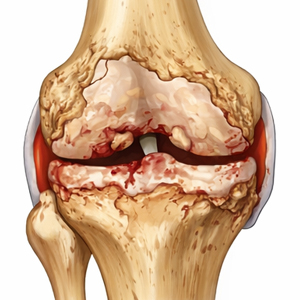

Arthrose ist kein rein mechanischer Verschleiß – sie ist ein komplexer, biologisch aktiver Prozess.

Was ist Arthrose?

Arthrose ist eine degenerative Erkrankung des Gelenkknorpels.

Im Verlauf kommt es zu einem fortschreitenden Abbau der Knorpelstruktur, Veränderungen des Knochens unter dem Gelenknorpel sowie entzündlichen Reizreaktionen der Gelenk-Innenhaut.

Was ist Arthrose

Arthrose wird in die Stadien I bis IV untergliedert

Stadium I

Leicht

Knorpelverlust

Stadium II

Mäßige Arthrose

Gelenkspaltverengung

Stadium III

Fortgeschritten

Lücken im Knorpel

Stadium IV

Schwere Arthrose

60% des Knorpels verloren